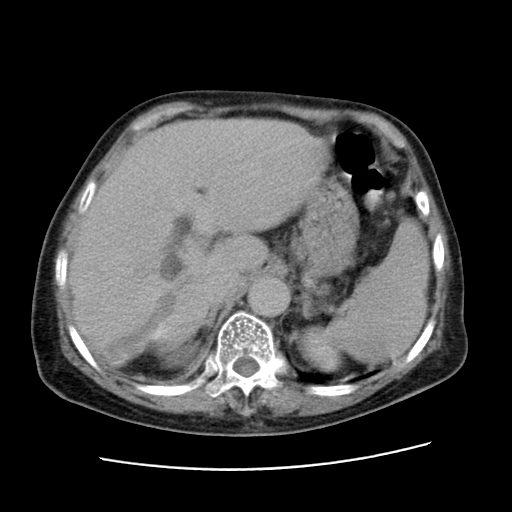

女,77.无不适

肝脏变异、异位胆囊,肝右叶肝内胆管结石并肝内胆管扩张。

肝内胆管扩张,胆囊炎,胆囊窝积液。 右侧胸腔少量积液。

肝右叶肝内胆管结石并肝内胆管扩张。

肝右叶肝内胆管结石并肝内胆管扩张。胆总管下段梗阻,考虑壶腹部占位。

右侧肝内胆管局限性扩张,其内密度不均匀,扩张的胆管壁增厚,考虑肝内胆管炎合并结石可能性大